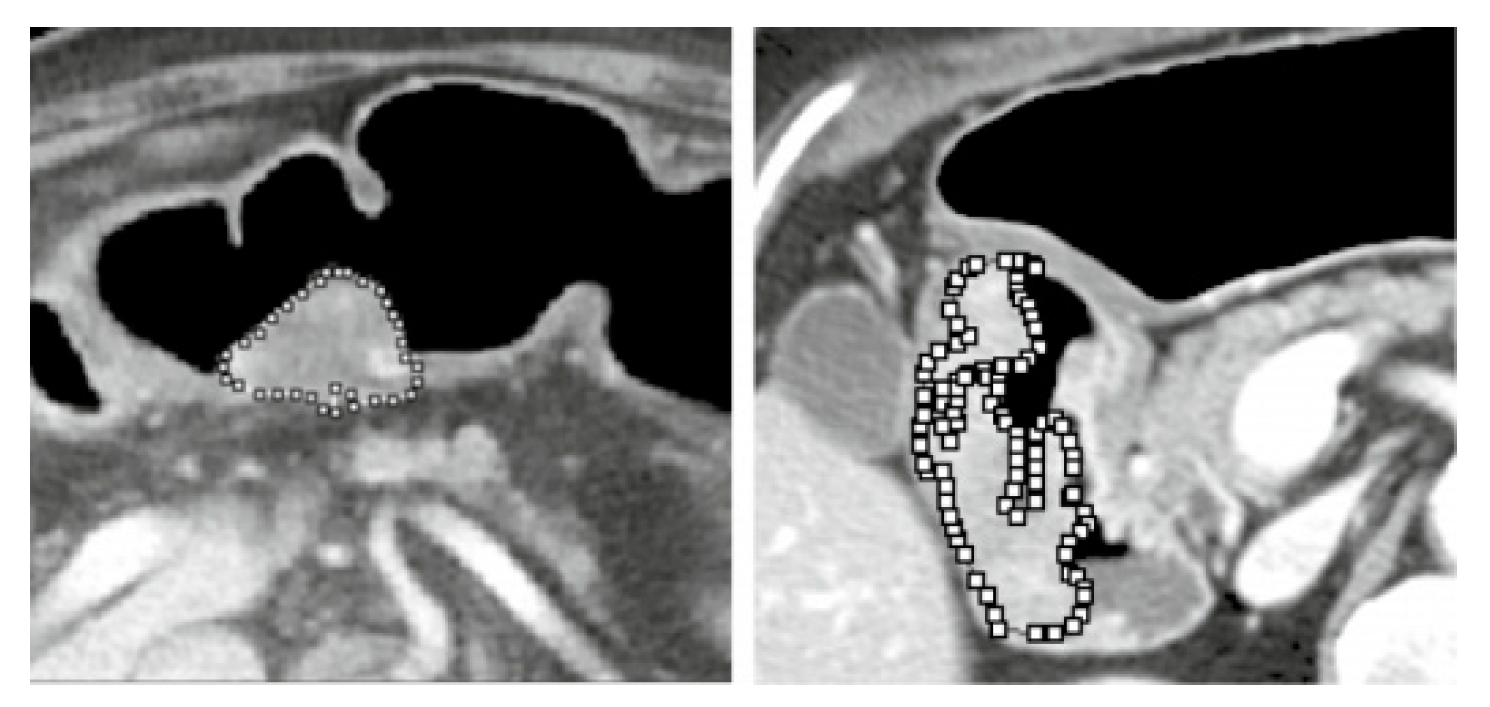

Use Of The Methods Of Segmentation C-Means, K-Means And Fractal Geometry In The Study In Alive Of the Cancer Of Lung (12).

- Rivero Borja, Mario Andres, and Jose Eduardo Escobar Martinez. “Uso de los métodos de segmentación c-means, k-means y geometría fractal en el estudio in vivo del cáncer de pulmón.” (2020).